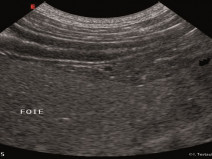

Du 12 au 13 mars 2017Chamonix-Mont-Blanc (74400)Médecine InterneRhône-Alpes, G.E.M.I.159Echographie du tube digestif et de ses annexes (foie - pancréas) - MODULE SATELLITE A : Nantes

Le plan de formation est composé d’un module central et de trois modules satellites.

L’objectif du module central est d’instaurer un protocole standardisé pour l’examen échographique de l’abdomen. Les bases théoriques et pratiques de l’échographie, la topographie abdominale et l’aspect échographique normal des organes abdominaux seront également repris.

Les modules satellites se...